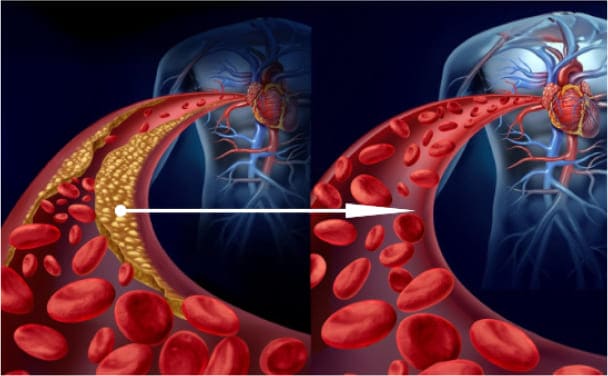

Masa trombótica

Los coágulos de sangre suelen pesar mucho menos de lo que se podría esperar, generalmente entre 800 gramos y 1 kg. Su principal peligro radica en su inestabilidad. En cualquier momento, un trombo (un coágulo de sangre) puede desprenderse y viajar por el torrente sanguíneo, lo que podría provocar bloqueos potencialmente mortales.

Si un trombo es lo suficientemente grande, puede obstruir completamente un vaso sanguíneo, cortando el suministro de sangre al órgano que nutre. Esta condición se conoce como isquemia.

Un accidente cerebrovascular isquémico ocurre cuando se bloquea un vaso sanguíneo en el cerebro. Un infarto de miocardio, o ataque cardíaco, ocurre cuando hay una obstrucción en una arteria coronaria del corazón. Otros órganos también pueden verse afectados por la isquemia. Por ejemplo, bloqueos en el hígado pueden llevar a isquemia hepática, mientras que bloqueos en los pulmones y los riñones pueden provocar fallos en estos órganos. Las hemorroides, de hecho, son una forma de isquemia vascular que afecta la región rectal. Por último, si los vasos sanguíneos de las piernas se bloquean, con el tiempo puede producirse la muerte de los tejidos, una condición conocida como gangrena.